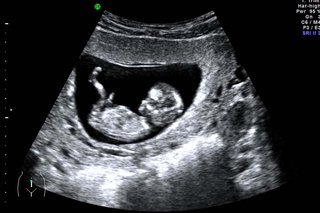

An NT scan (Nuchal Translucency scan) is a special ultrasound done during early pregnancy to measure the fluid-filled space at the back of a baby’s neck.

- When is it done? Between 11 and 13 weeks + 6 days of pregnancy

Assesses Overall Early Development

- Confirms baby’s growth

- Checks heartbeat

- Confirms due date